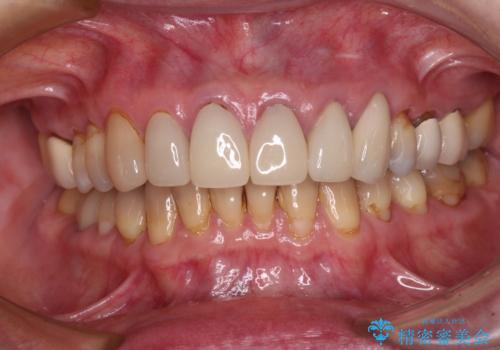

もげてしまった前歯をセラミッククラウンで自然に

外れてしまったクラウンを保管しておき、新しいクラウン製作の際に技工所に送ることで、今までと同じような色合いに仕上げることができ、周囲のクラウンとバランスを取ることができます。